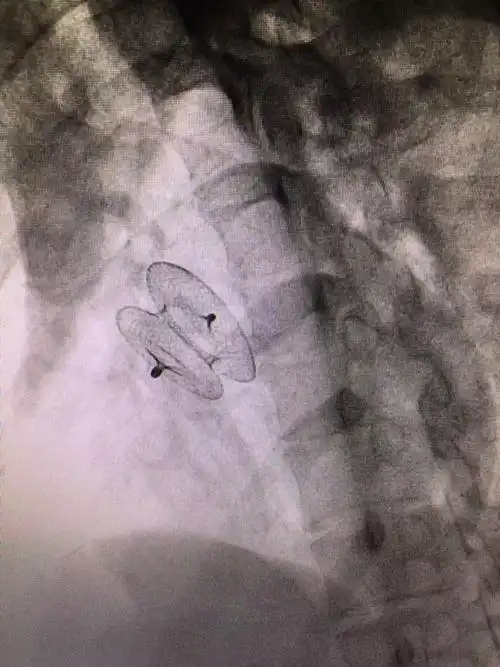

小女孩先心病,微创手术,右侧腋下小切口

右侧腋下超小微创切口3,大于6毫米的室缺属于大型室缺,不但肺动脉压会